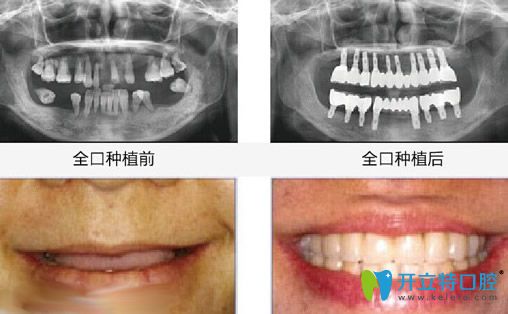

昆明竹子口腔怎么樣?國醫(yī)生All-on-4即刻種植牙案例效果來見證:

種植前:牙齒幾乎掉完,只剩下殘牙根;

種植后:無論是咀嚼力度,還是外觀都和真牙一樣。

昆明竹子口腔<!--<i data=20240703-sp></i>-->國醫(yī)生全口種植牙案例效果